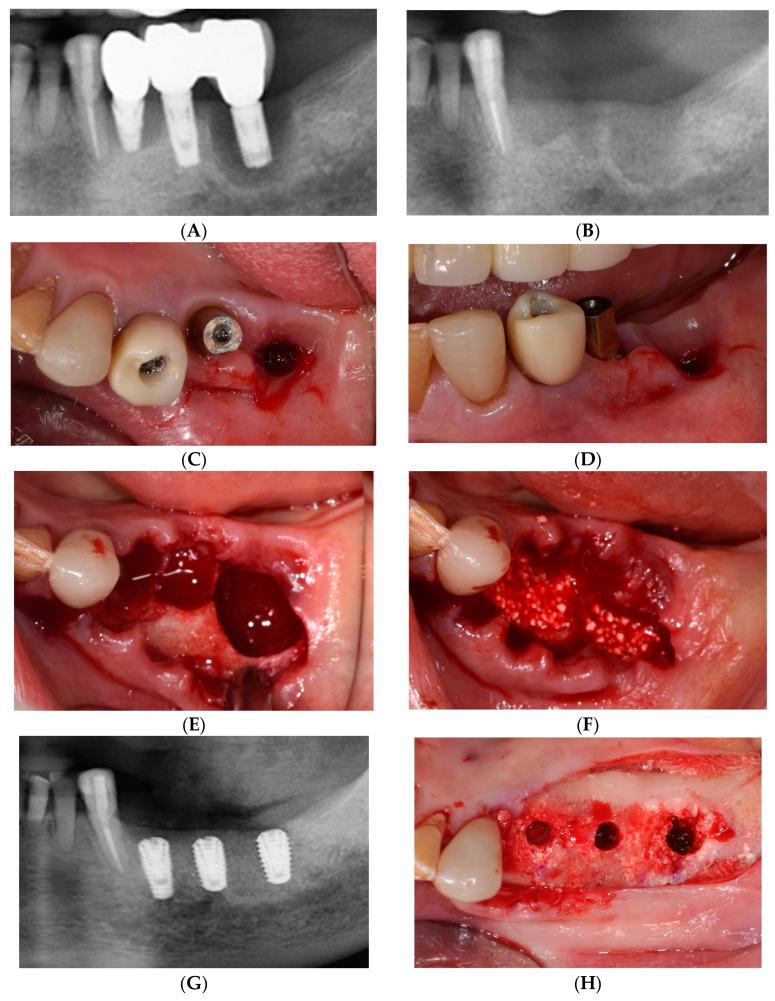

Free gingival graft (FGG) is the gold standard procedure for the reliable augmentation of lost keratinized mucosa (KM) around dental implants. This conventional surgical approach has its drawbacks, including limitations in manipulation, the requirement for suturing, postoperative discomfort, and pain. This case report aimed to evaluate the efficacy of a simplified free gingival graft (sFGG) in addressing the issue of inadequate keratinized mucosa around dental implants. Fixation tacks were used to perform the sFGG procedure. Initially, a partial-thickness flap was created and apically repositioned. The gingival graft was harvested from the palate with a narrow profile and securely affixed to the recipient site using 5 mm long fixation tacks. Significant gains in keratinized mucosa were achieved and successfully maintained within 1 year. Consequently, the sFGG technique emerges as a simple and reliable treatment approach for managing inadequate keratinized mucosa around dental implants.

游离龈瓣移植术(FGG)是可靠增加牙种植体周围丧失角化黏膜(KM)的金标准方法。这种传统的手术方法有其缺点,包括操作限制、需要缝合、术后不适和疼痛。本病例报告旨在评估简化游离龈瓣移植术(sFGG)在解决牙种植体周围角化黏膜不足问题上的疗效。固定钉用于进行 sFGG 手术。首先,创建一个部分厚度的皮瓣并向根尖方向重新定位。从 palate 中获取具有窄轮廓的龈瓣,并使用 5mm 长的固定钉将其牢固地固定在受体部位。获得了显著的角化黏膜增加,并在 1 年内成功维持。因此,sFGG 技术是一种简单可靠的治疗方法,用于管理牙种植体周围角化黏膜不足的问题。